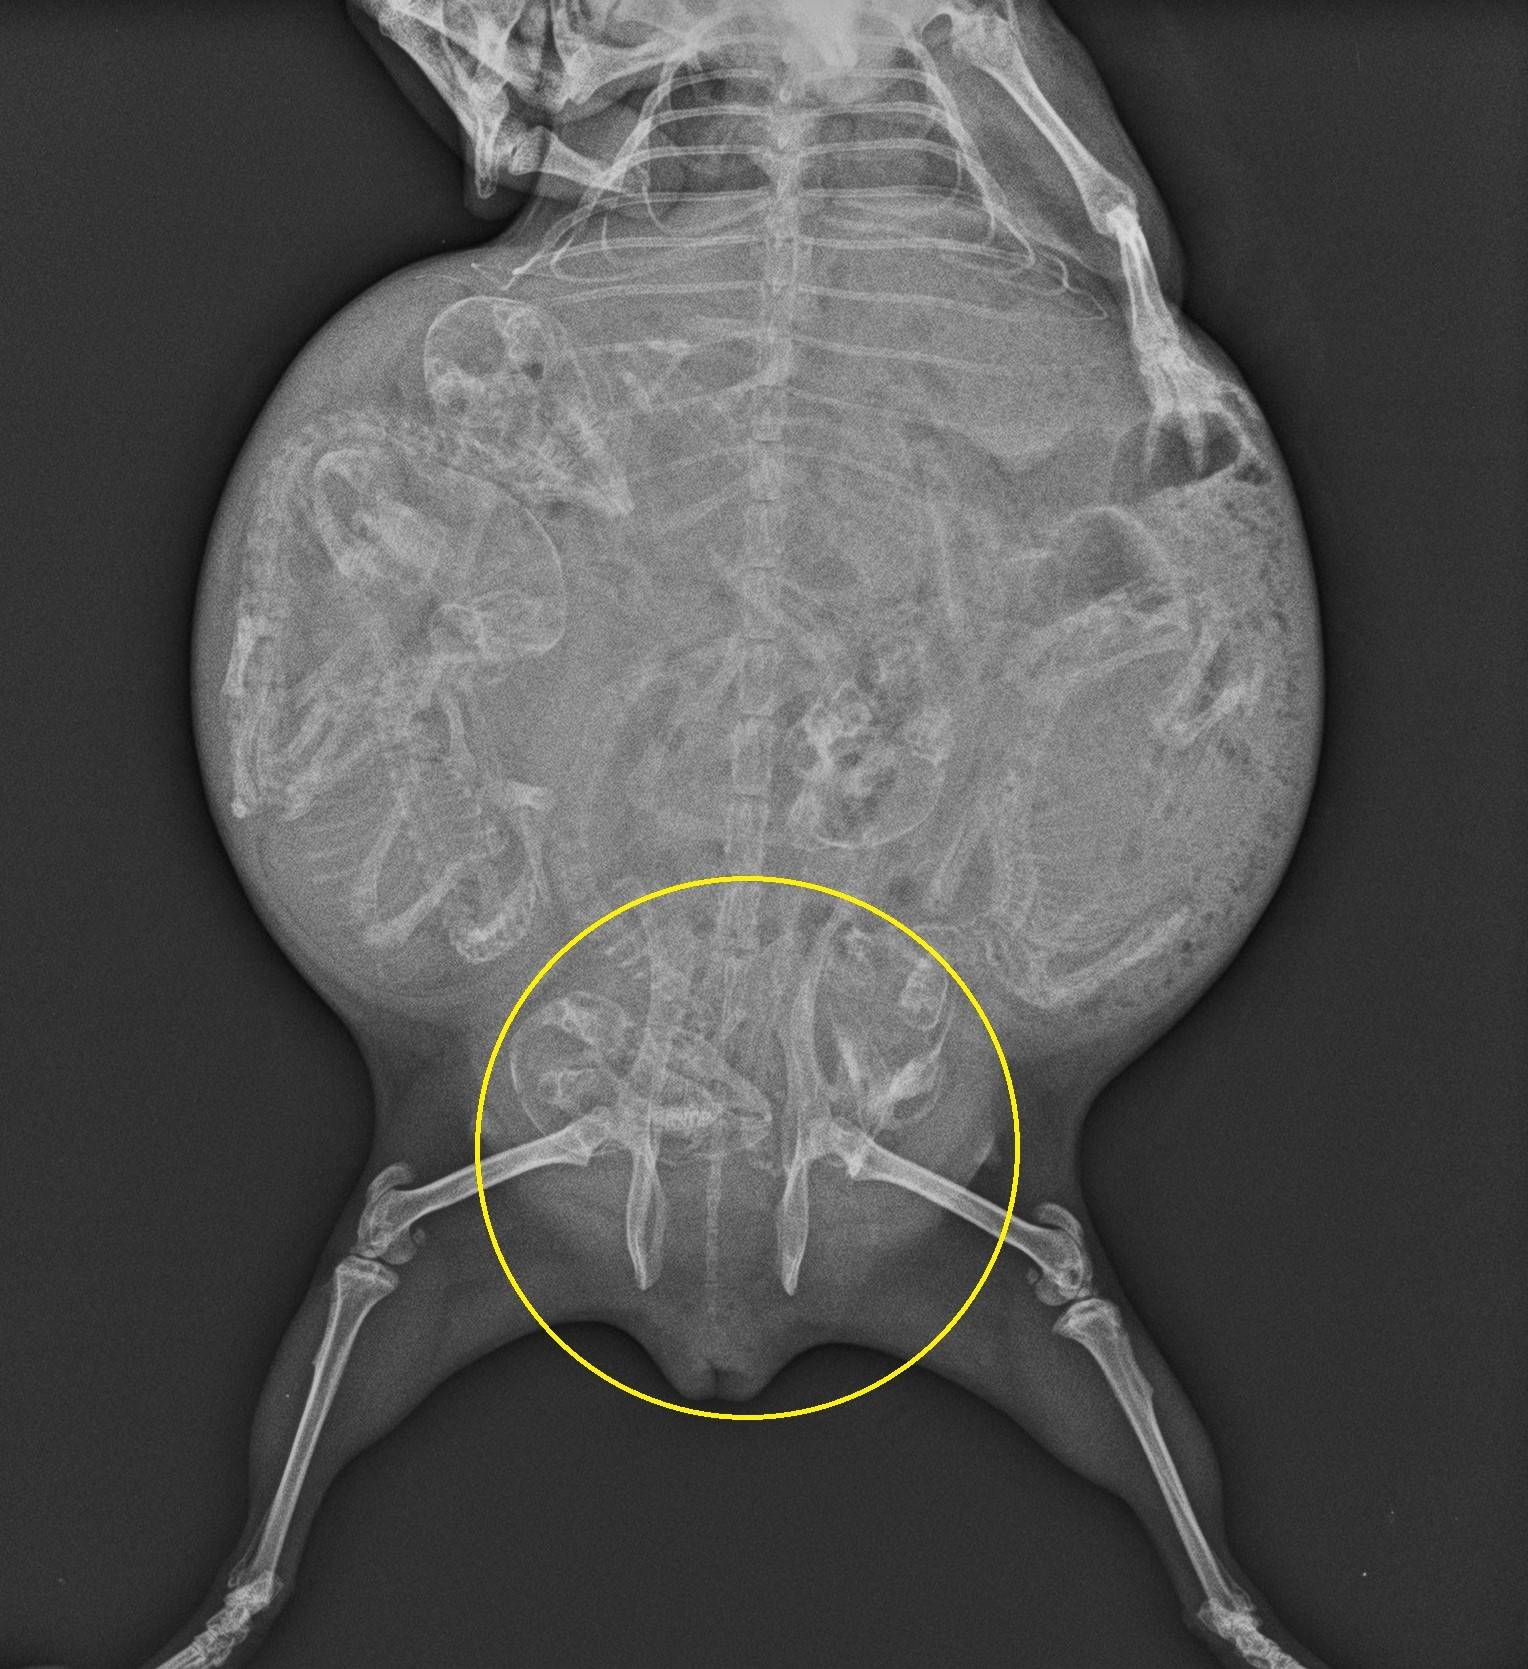

レントゲンでは、骨盤の恥骨結合が1.5㎝以上開き、出産が近いことがわかります。モルモットの成書によると、恥骨結合が1.5㎝まで開くと48時間以内に出産すると言われています。

ちなみに、これはまだ恥骨結合が開いていないレントゲン写真です。

比べるとわかりやすいですよね。